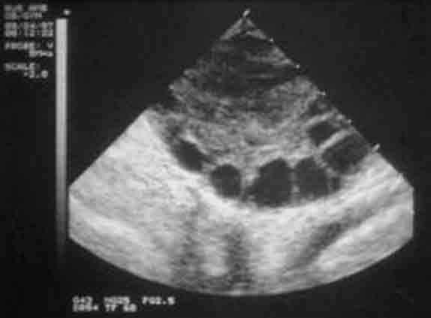

成熟卵泡的B超表現:

1、卵泡呈圓形或橢圓形,直徑達15-30mm(21.2+-0.53mm),卵泡內呈無回聲區,清亮純凈,邊界清晰,壁菲薄。

2、20%成熟卵泡在排卵前一天,可見卵丘圖像,在卵泡內近壁處呈短強回聲。